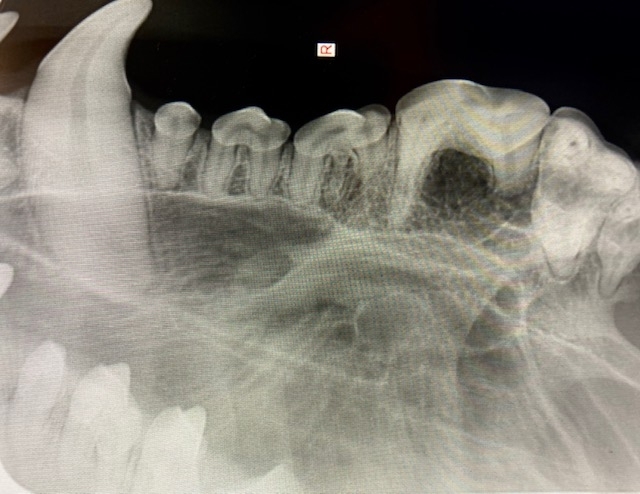

- advanced dental X-rays

Dental and Maxillo-facial surgeries